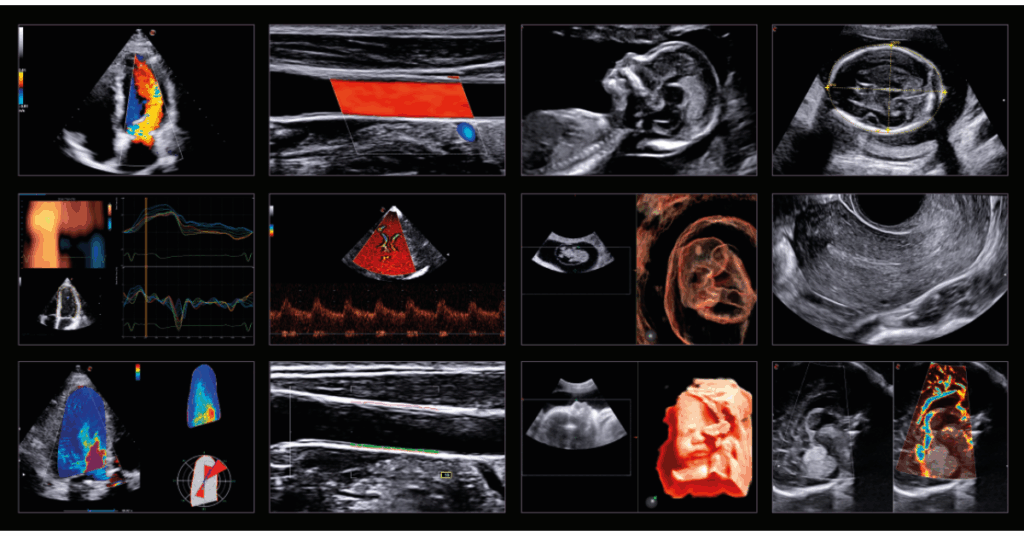

MyLab™X9 posouvá hranice ultrazvukové diagnostiky díky kombinaci nejmodernějších technologií, vysokému rozlišení a umělé inteligenci. Přístroj poskytuje optimální kvalitu obrazu i v nejnáročnějších klinických podmínkách, čímž zajišťuje přesnější a rychlejší diagnostiku napříč medicínskými obory.

Komplexní řešení umožňuje detekci, sledování a léčbu širokého spektra onemocnění – od hepatologie a urologie, přes radiologii, gastroenterologii, gynekologii až po sportovní medicínu. Technologie, jako fúzní zobrazování (US-MRI), Virtual Navigator nebo UroFusion, podporované umělou inteligencí, poskytují přesné vedení intervencí a cílených biopsií v reálném čase.

Díky funkcím jako BreastNav™MRI, QPack, QElaXto 2D či Single Crystal sondám nabízí MyLab™X9 dokonalé zobrazení měkkých tkání, vaskularizace i strukturálních detailů s frekvencí až 25 MHz.